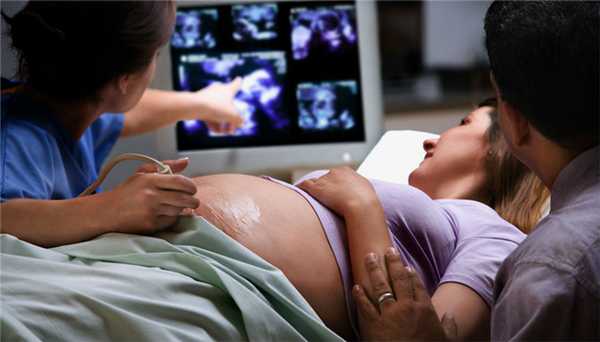

Эхо кг плода является современным методом диагностики сердечно-сосудистой системы. Суть метода заключается в определении возможных патологических изменений в формировании сердца плода, которые визуализируются при помощи высокочастотных волн. Процедуру проводят по показаниям, в тех случаях, когда во время прохождения плановой УЗИ диагностики у беременной было выявлено отклонения от нормы. Какие ещё существуют показания к проведению исследования, и как оно осуществляется?

Основная характеристика метода

Эхокардиография плода - это не инвазивный метод исследования, способный визуализировать сердце и сосуды в период внутриутробного развития ребенка при помощи ультразвуковых волн. Современные технологии позволяют применять в пренатальной диагностике высокоточные и безопасные аппараты, которые гарантируют безопасность при проведении данного исследования.

Как осуществляется процедура?

Сделать эхо кг можно с помощью цветного аппарата ультразвуковой диагностики и прибором для допплерографии. На ранних сроках вынашивания ребенка применяется вагинальный метод исследования матки. Длительность процедуры составляет около 40-45 минут, однако при подозрении на патологию диагностика может несколько продлиться.

Алгоритм того как, делают эхо кг плода:

- Женщина принимает горизонтальное положение на спине с вытянутыми ногами.

- На область живота наносится небольшое количество геля, улучшающего качество визуализации органов на мониторе.

- Затем на животе беременной закрепляется датчик.